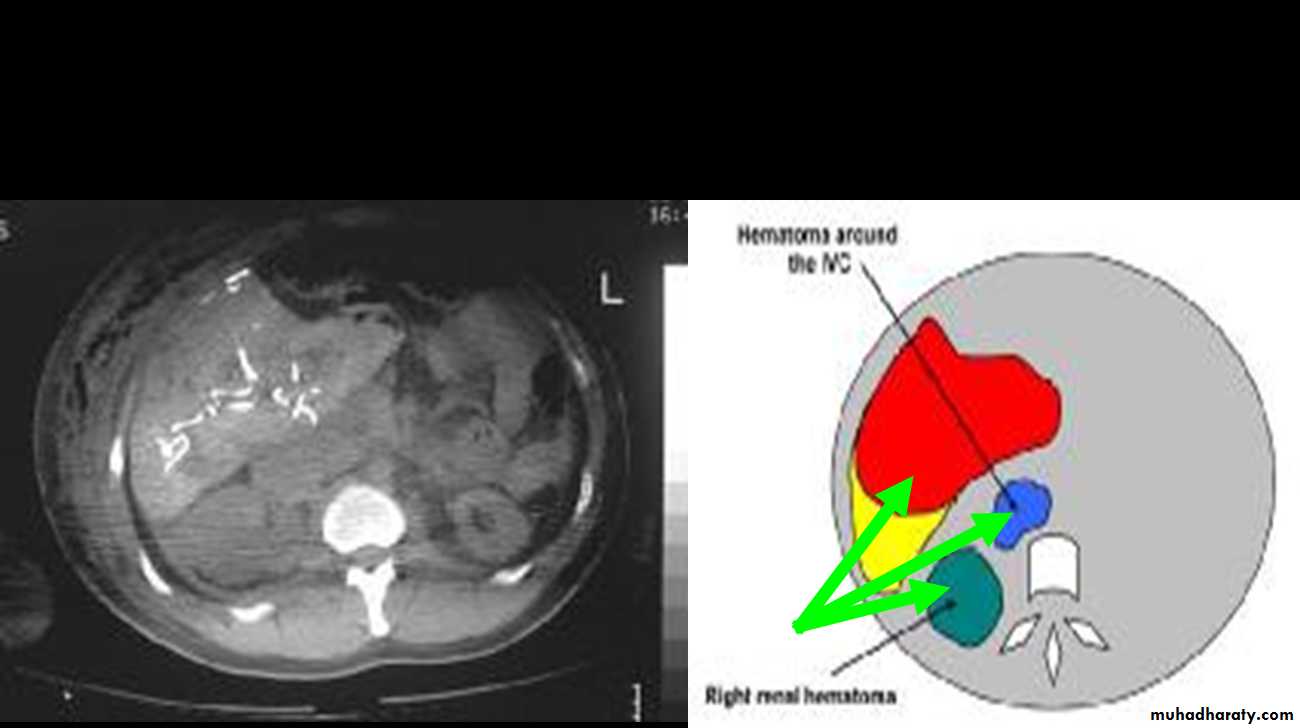

CT Scans

Accurate in localizing the site of liver injury and any associated injuries

Used to monitor healing

CT criteria for staging liver trauma uses AAST liver injury scaleGrades 1-6